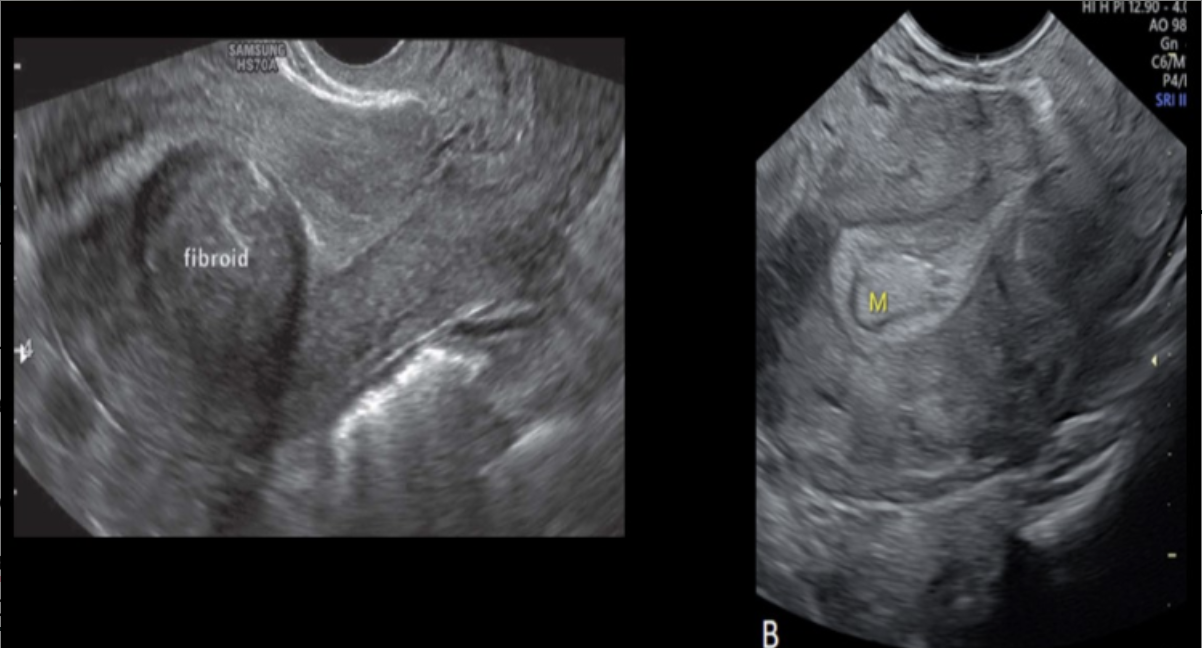

where is the fibroid in the sag uterus

a) posterior fundal

b) posterior body

c) anterior fundal

d) anterior cervix

what type of fibroid is this

a) pedunculated

b) subserosal

c) submucosal

d) intramural